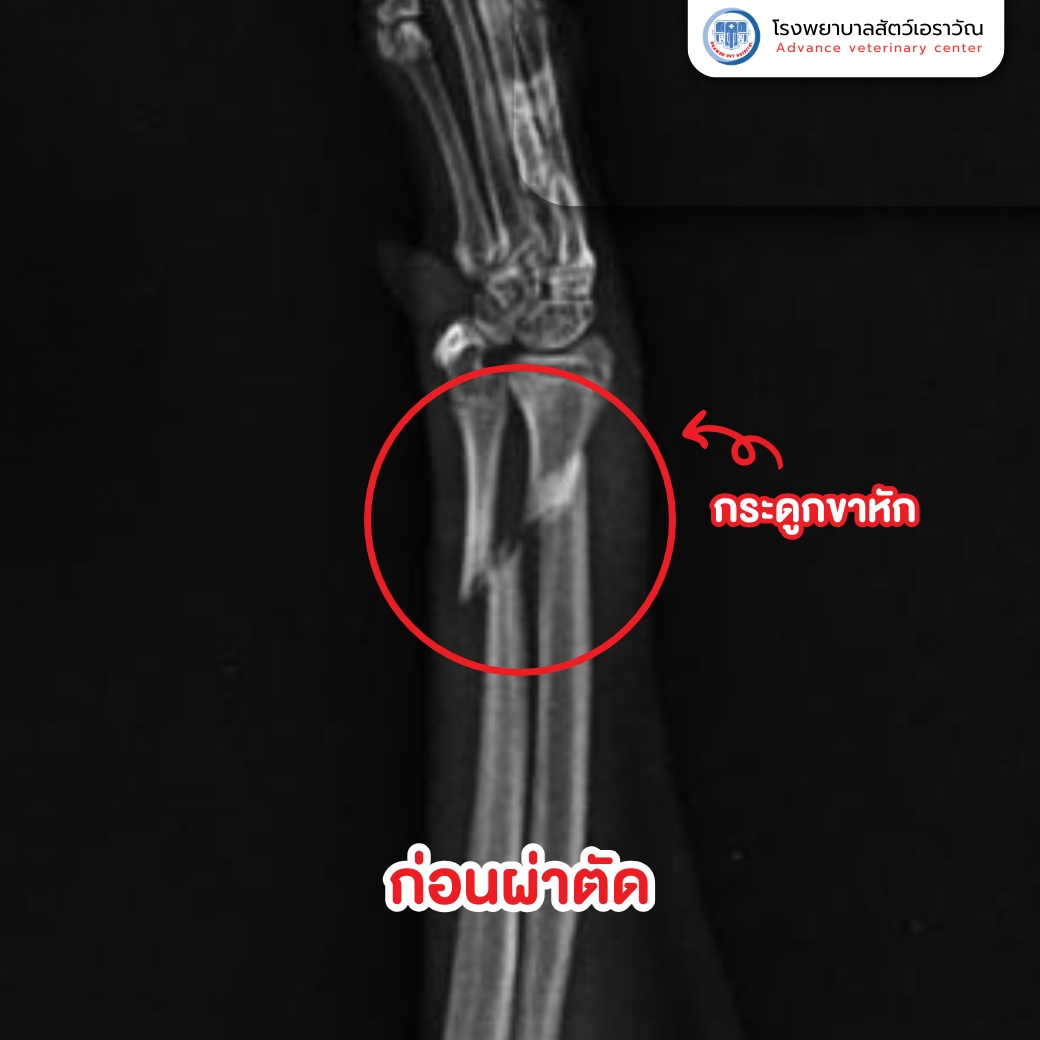

ไม่นานมานี้ มีเจ้าของท่านหนึ่งพา น้องแมว มาที่โรงพยาบาลของเรา หลังจากพบว่าน้องมีอาการ ยกขา ไม่ลงน้ำหนัก และส่งเสียงร้องเมื่อจับบริเวณขา จึงพาไปตรวจที่คลินิกใกล้บ้านและพบจากการเอกซเรย์ว่า กระดูกขาหน้าหัก เจ้าของจึงตัดสินใจส่งน้องแมวมารักษาต่อที่ โรงพยาบาลสัตว์เอราวัณ

เมื่อมาถึง ทีมสัตวแพทย์ของเราได้ทำการ ตรวจวินิจฉัยอย่างละเอียด ทั้งจากผลเอกซเรย์และการประเมินสภาพร่างกาย โดยพบว่า กระดูกที่หักอยู่ในตำแหน่งที่ต้องผ่าตัดและใส่อุปกรณ์ยึดกระดูกภายใน เพื่อให้น้องแมวสามารถฟื้นตัวได้เร็วและกลับมาใช้ชีวิตตามปกติ